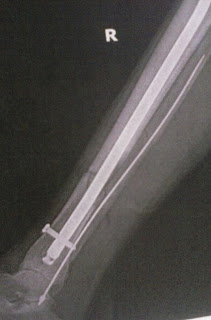

I was brought to the hospital, surgery to clean the wound was performed, I rested for a day and underwent a 2nd 4 hour surgery to insert a nail through my tibia and a wire through my fibula. The old hard ware from the previous ankle break in 2015 was in the way of the new, so they took it out and gave it back to me. Hex head self tapping screws and a plate: titanium. Look away if the photos below will make you queazy.

There was enough bone loss that there is a question if there is enough bone to bone contact for healing to occur. If not it will require a bone graft in about 6 weeks. If I do heal on my own it will be 6 months before I can walk. I worked four jobs: a handy ma'am, with the local stage hand union, running my business, Pedal Promotion, and as a model. I will be able to continue 2 of the 4. It would be really fantastic if more clients hire my business because not only would it keep some income coming in for me personally, but also pay the people who work for me $15 an hour. I am so deeply thankful that I built my house, so that even when horrible things like this happen I know I can reply on the stability of my housing. I have recovered from one major injury there, and in that case I didn't have the use of my upper body strength, and my home wasn't nearly so complete. Also, having stabilized the cost of my living expenses means that I can buy higher quality food to rebuild my body with.